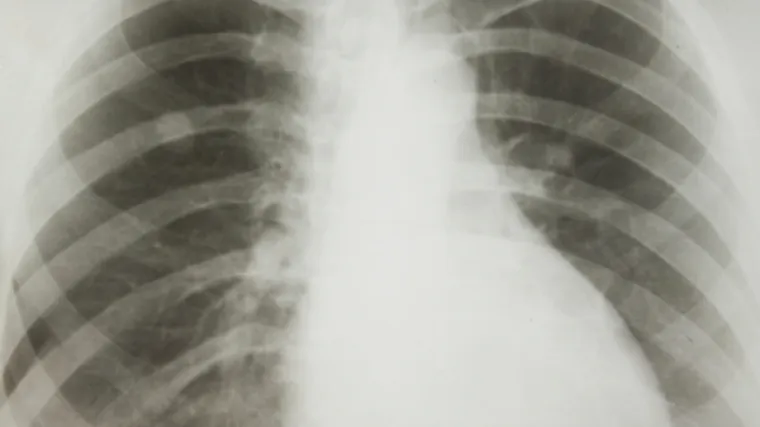

Dobre vijesti iz SAD-a: lijek AstraZenece odobren kao lijek prvog izbora za rak pluća!

Američka uprava za hranu i lijekove (FDA) odobrila je u ponedjeljak preparat "Iressa" kao lijek prvog izbora za liječenje jedne vrste raka pluća.

Prema priopćenju FDA odobrenje je izdano na temelju rezultata kliničkog ispitivanja na 106 pacijenata koji prethodno nisu liječeni, a dijagnosticiran im je tzv. ne-mikrocelularni rak pluća.

Ranije je lijek bio odobren samo za liječenje pacijenata koji nisu dobro reagirali na kemoterapiju.

Rak pluća vodeći je uzrok smrti od karcinoma u SAD-u i prema procjenama Nacionalnog instituta za borbu protiv raka ove će godine od te bolesti umrijeti više od 158.000 ljudi.